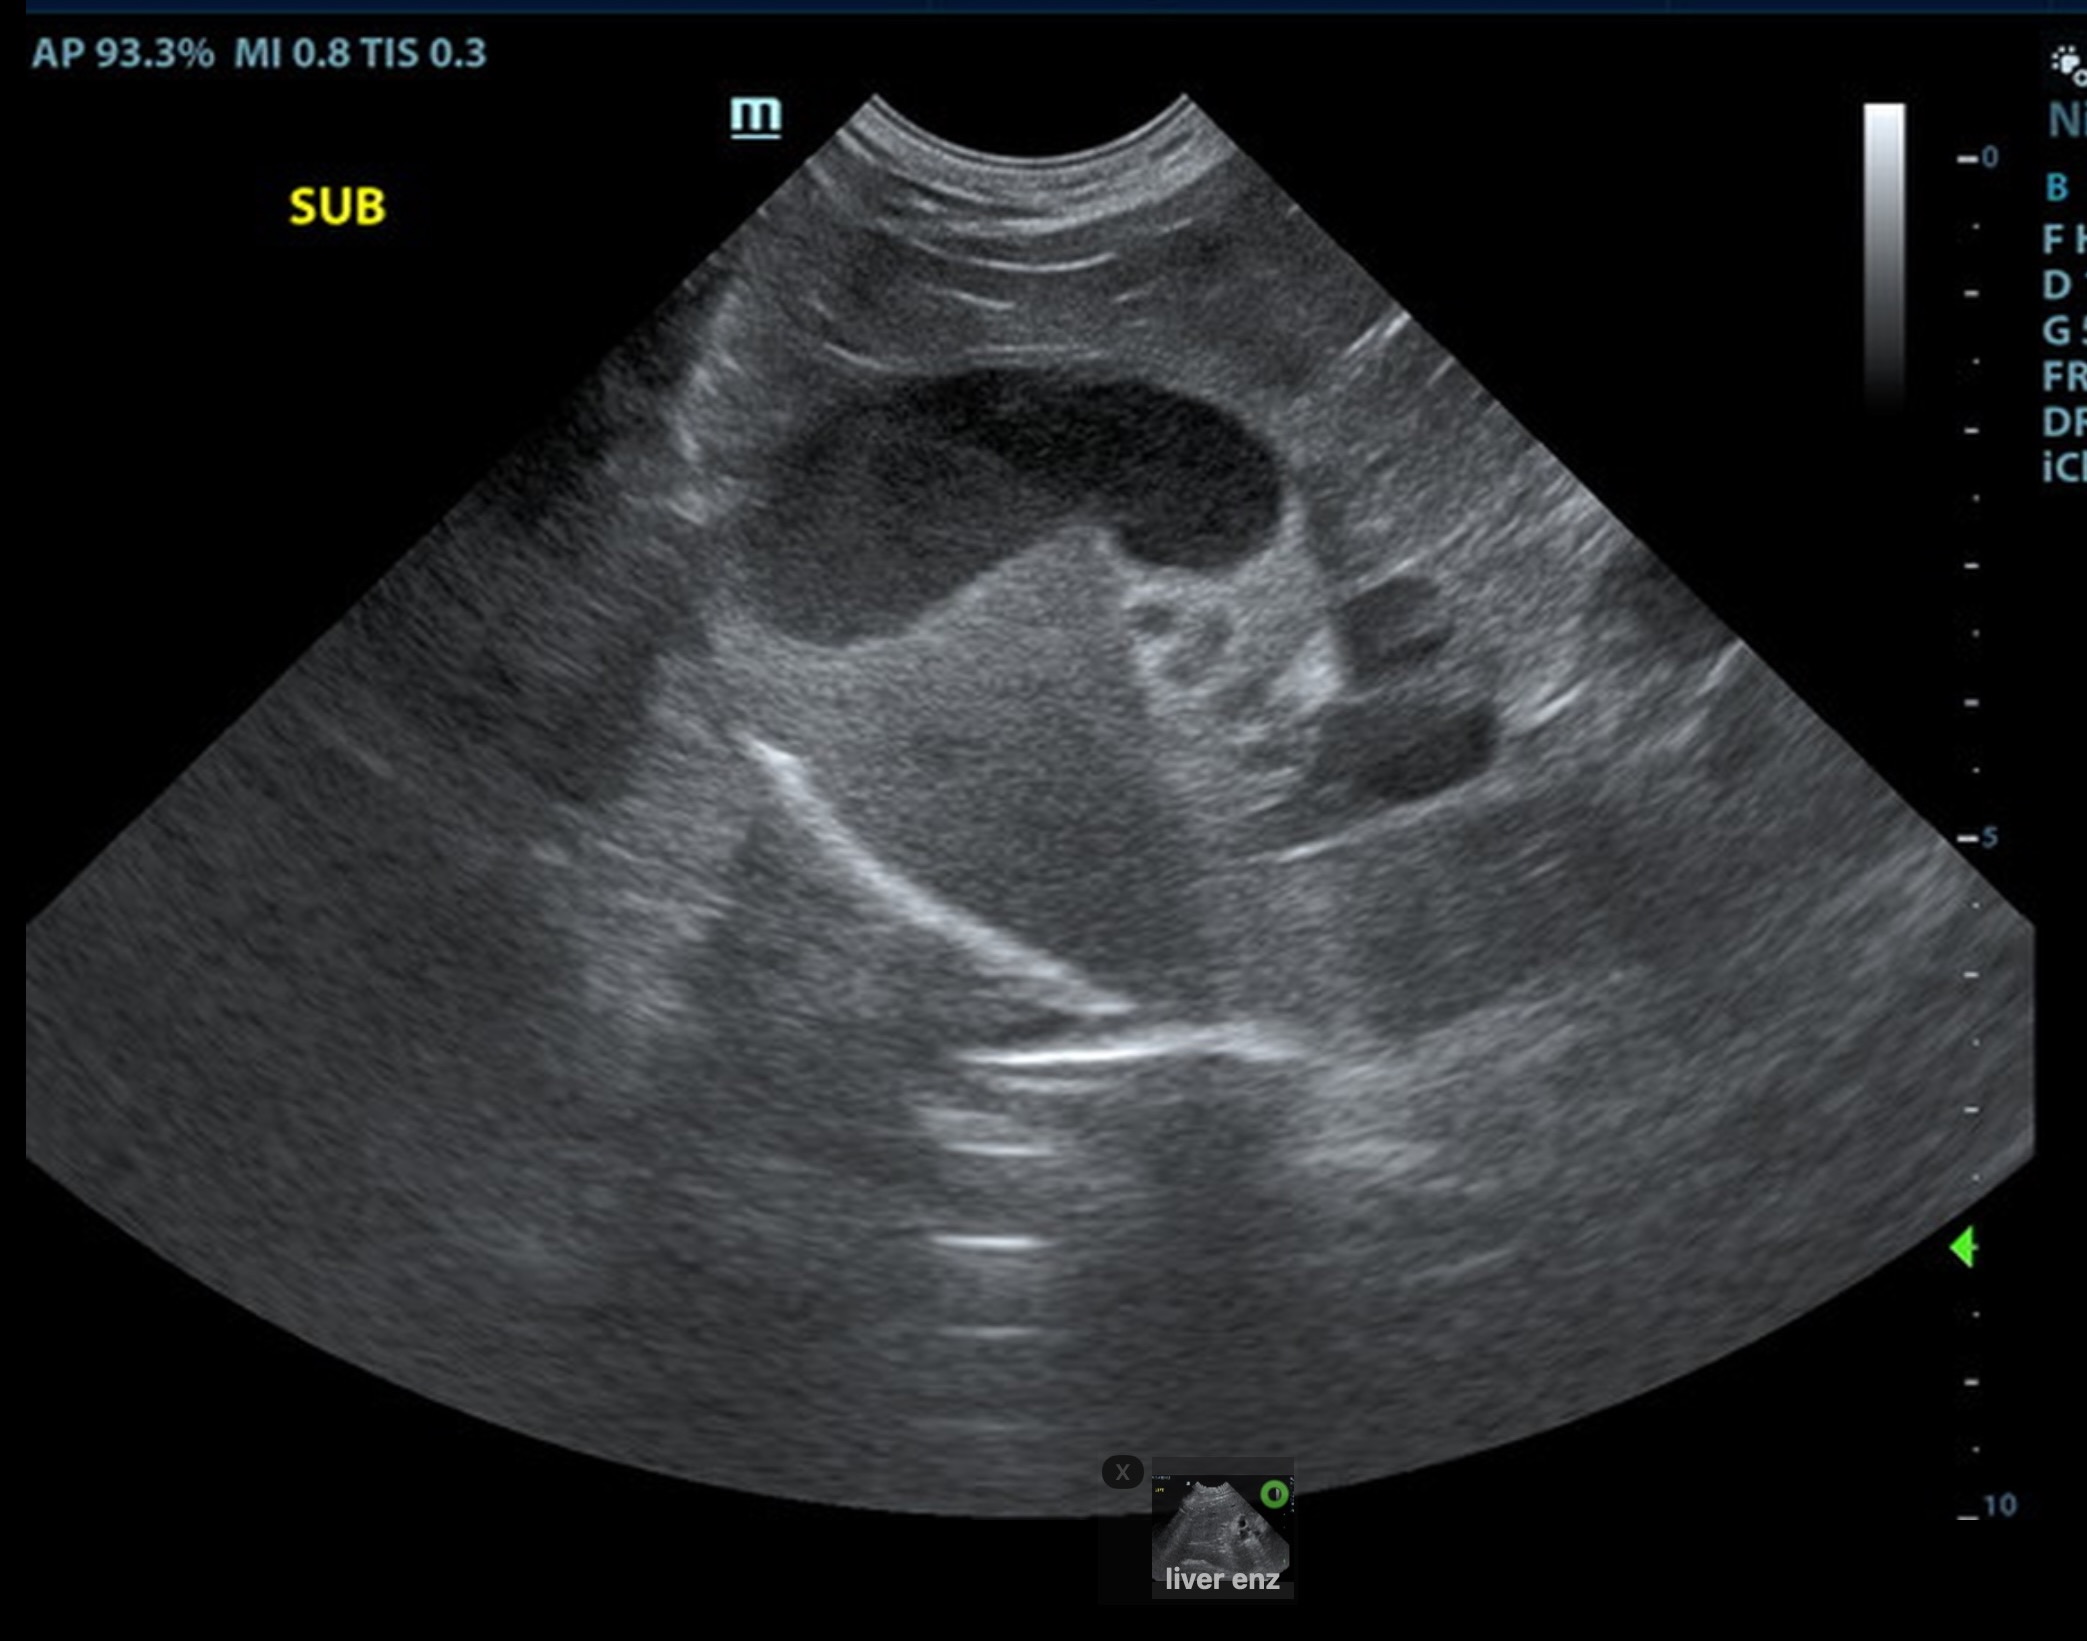

Local biliary duct dilation noted with post hepatic obstruction. Gallbladder was turgid. The common bile duct (CBD) was dilated with echogenic debris or possible tissue proliferation. The CBD measred 0.86 cm. An overt mass was noted at the common bile duct termination, measuring 2.0 cm. Target-type nodules noted in the liver.